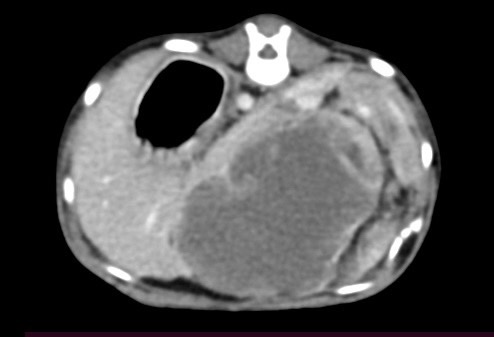

貓咪 卵巢殘留

在他院絕育後仍有發情現象,轉院至築心,經由電腦斷層掃描確認後手術。

卵巢殘留

卵巢殘留是指雌性動物在進行絕育手術後,仍然有部分卵巢組織殘留,進而導致術後仍然反覆發情,並可能繼發子宮殘端蓄膿、乳腺腫瘤等疾病。而殘存的卵巢,由於體積小且子宮角已被摘除,往往難以找尋。幸而隨著動物醫療進步,依靠電腦斷層、內視鏡等先進設備,卵巢殘留的情況已不再難以處理。

小花是一隻一歲多的母貓,半年前曾在其他醫院做過絕育手術,但手術當下卻只找到單側的子宮卵巢,且在這半年當中仍然反反覆覆地發情,讓飼主十分擔心,於是來到築心尋求治療。在了解小花的狀況後,我們為小花安排了電腦斷層掃描,並在腹腔的左側發現了疑似殘存的卵巢影像(見圖示),接著,在影像定位的協助下順利開腹取出殘存的卵巢和發育異常子宮角,而在殘存的子宮內已然形成了子宮蓄膿。

幸虧子宮蓄膿的情形尚不嚴重,並沒有造成感染範圍的擴散,手術後經過一小段時間的修養,小花目前已經順利拆線,在家過著無憂無慮的生活囉。